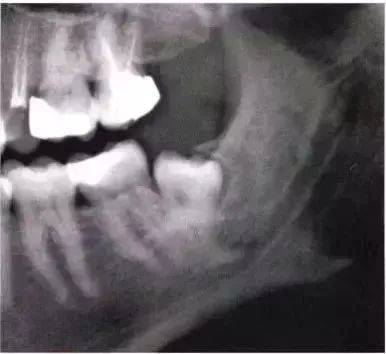

远中倾斜第三磨牙 第Ⅰ类 第Ⅱ类 第Ⅲ类 手术的难易程度主要取决于骨的因素。手术的难度随埋伏深度的增加而增加。第Ⅰ、Ⅱ及第Ⅲ类阻生牙与第二磨牙和下颌升支之间的距离相对应。 部分远中阻生的左下颌第三